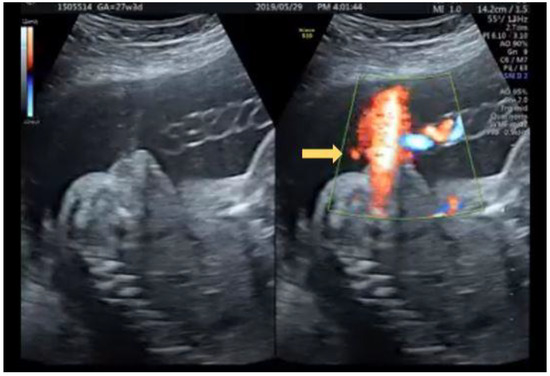

2.1. Case 1